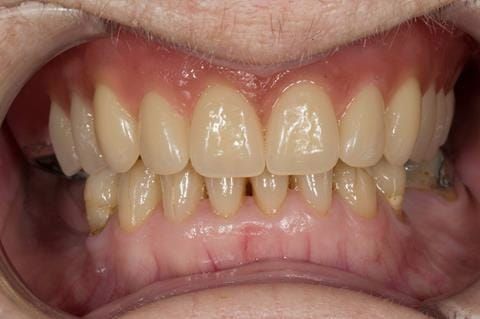

Following consultation and second discussion appointment the patient chose to have option 2 namely, a window denture - maxillary cobalt chromium based partial denture. The clinical situation and treatment process is shown in detail below with photographs. The patient was successfully rehabilitated with this and her quality of life considerably improved. The clinical work was provided by Finlay and the technical work by Rowan.